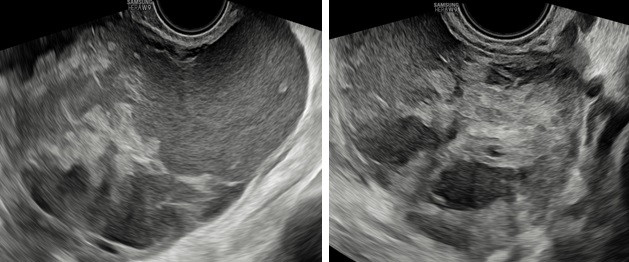

– Siêu âm: Tử cung và buồng trứng (T) bình thường, buồng trứng (P) không quan sát thấy. Từ cùng đồ sau lan qua hố chậu (P) có 1 khối echo hỗn hợp không đồng nhất, kích thước# 105x 98x 59 mm, bên trong có nhiều mảng echo dày bờ không đều, di động khi di chuyển đầu dò, có tăng sinh mạch máu mức độ 3 Ở ngoại vi khối này có hình ảnh mô buồng trứng bình thường. Dịch cùng đồ# 8 mm.

– Chẩn đoán siêu âm: Theo dõi khối huyết tụ thành nang (HTTN) chưa loại trừ khả năng: u đơn thùy buồng trứng (P) có mảng xuất huyết bên trong.

Hình 2: Mặt cắt dọc và ngang qua ngã âm đạo thấy khối u có phản âm hỗn hợp, bên trong có nhiều mảng phản âm dày, di động khi di chuyển đầu dò, giúp hướng đến bản chất xuất huyết.